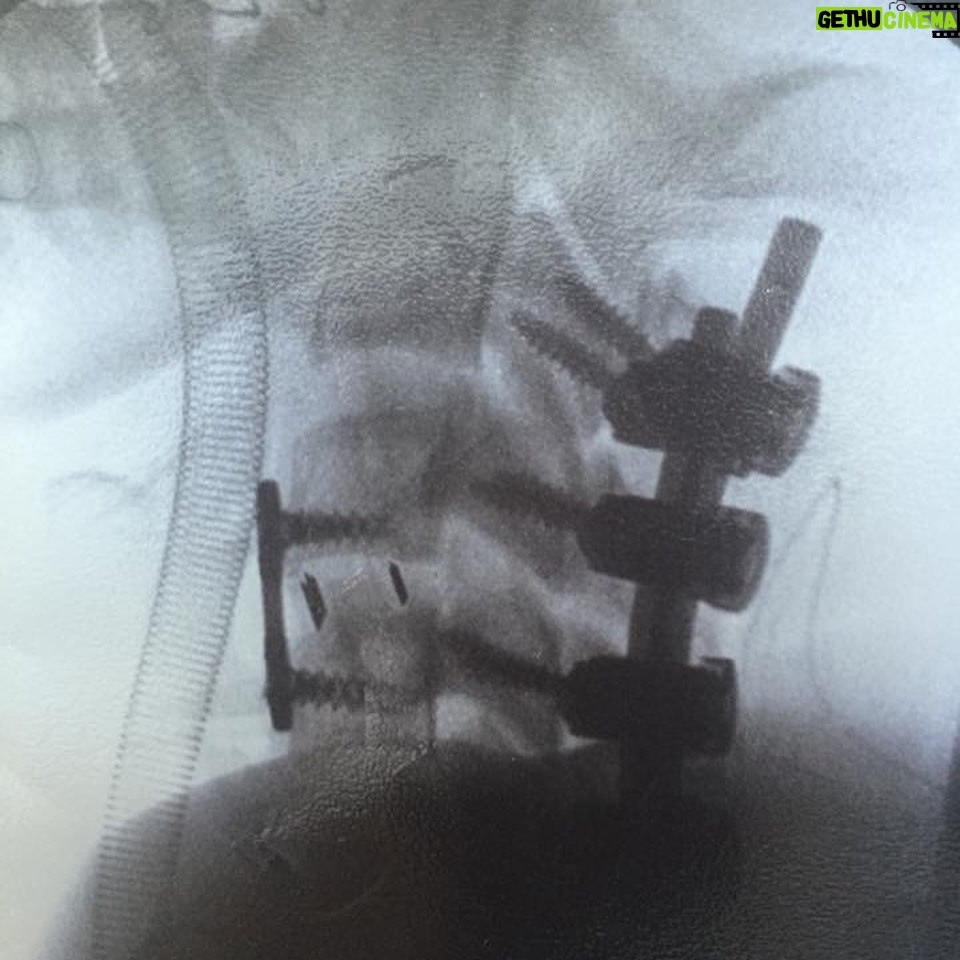

Caption : 9 years ago, I broke my neck. 15 years ago, I stubbed my toe. 20 years ago, I lost my favourite toy car. Trauma can always be overcome.Likes : 55736

55.7K Likes – George Robinson Instagram

Caption : 9 years ago, I broke my neck. 15 years ago, I stubbed my toe. 20 years ago, I lost my favourite toy car. Trauma can always be overcome.Likes : 55736

55.7K Likes – George Robinson Instagram

Caption : 9 years ago, I broke my neck. 15 years ago, I stubbed my toe. 20 years ago, I lost my favourite toy car. Trauma can always be overcome.Likes : 55736

Caption : Hey guys, Thank you much for your lovely messages about season three. This is such an amazing show to be a part of and it is a huge honour to be able to bring Isaac to life. This is for anyone who is currently in hospital, just come out of hospital or is just feeling like they have nowhere left to go in life. I know what it’s like. I have been in exactly that position – wondering what my life is going to be after breaking my neck, tubes sticking out here there and everywhere. I’m here to say that it does get better and life can be just as beautiful and fulfilled as it was before. Thank you to everyone who has made this journey possible for me. There’s more to come. Thanks to @littletitan for the 📸Likes : 50232

Caption : Five years ago today I broke my neck. Silly me LOLLikes : 48440

Caption : eight years ago, I realised that standing up was overrated thanks to everyone who has helped and followed me on this weird journey.Likes : 48016

48K Likes – George Robinson Instagram

Caption : seven years ago today, I broke my neck it seems to have been a good career move in hindsightLikes : 47251

47.3K Likes – George Robinson Instagram